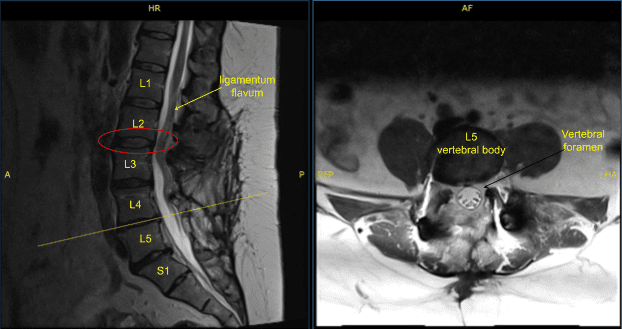

The patient was complaining of pain in both lower extremities. They had a history of L3 to S1 fusion done by another physician. Imaging studies showed good fusion mass from L3 to S1 but compression over L2-L3 segment with bilateral neural foraminal compression of L3 along with bony island formation over L3-L4 region with foraminal compression.

Disc bulge, facet osteoarthritis, buckling of ligamentum flavum